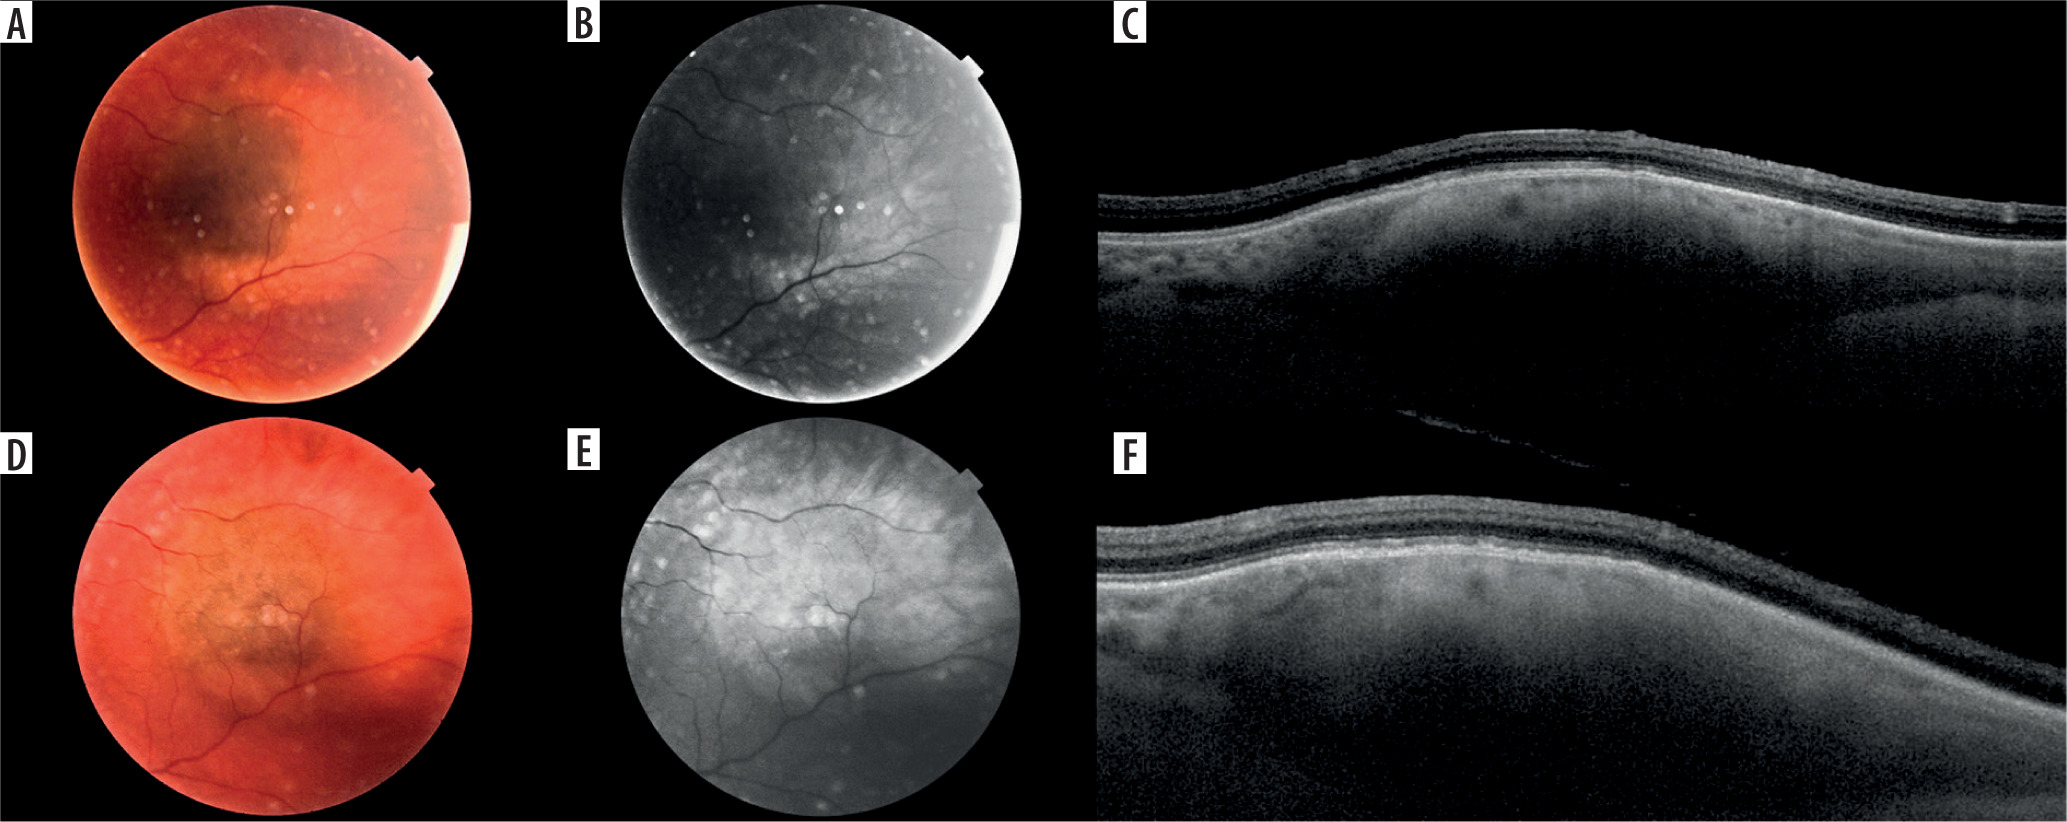

Figure 4

Melanocytic lesion found in 14-year-old patient, images at first visit: A) color fundus photography showing slightly elevated lesion accompanied by visible subretinal fluid (its margin lined with arrows); B) autofluorescence photography revealing presence of orange pigment and subretinal fluid (margin lined with arrows); C) OCT image of the lesion with accompanying subretinal fluid (arrow); MOLES score 4 (M-0, O-2, L-0, E-0, S-2) – urgent referral to ocular oncologist is recommended